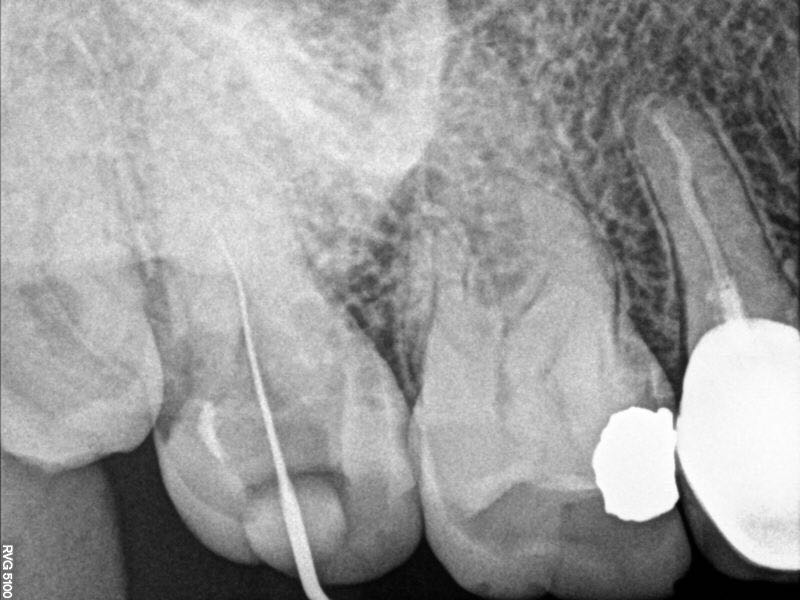

示踪片